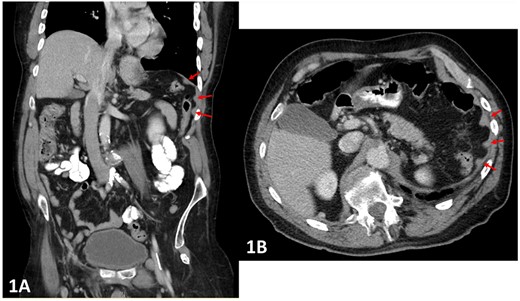

A 64-year-old male underwent an elective colostomy formation for obstructive defecation. The patient had a background of T12 spinal cord injury and resultant incomplete paraplegia from a motor vehicle accident 34 years prior. The same accident caused a traumatic splenic injury, resulting in splenectomy. A pre-operative CT abdomen and pelvis was completed before the elective procedure. This revealed multiple hyperdense peritoneal deposits ranging from 1 to 3 cm (Fig. 1A and B), and a biopsy was recommended. Intraoperatively, several deposits ranging from 1 to 3 cm were observed throughout the greater omentum, and biopsies were obtained for histological analysis. No intraoperative complications were encountered. However, the patient had intraabdominal bleeding on the first post-operative day and required a return to the theatre. Exploratory laparoscopy revealed multiple bleeding nodules in the omentum (Fig. 2) and a subsequent partial omentectomy was performed. There was no other source of intraabdominal bleeding on thorough re-inspection. Histopathology of the nodules was consistent with splenic tissue (Fig. 3A–C), confirming the suspicion of intraabdominal splenosis mimicking peritoneal carcinomatosis pre-operatively and causing the intraabdominal bleeding post-operatively. The patient developed a pulmonary embolism and required anticoagulation a week later. He recovered well from the operation and complicating pulmonary embolism, but he needed a short admission to a rehabilitation unit for physical conditioning. On follow-up, he is recovered and managing his colostomy well.

(A and B) Pre-operative CT abdomen (A—coronal, B—transverse planes) with multiple peritoneal nodules indicated by the arrows.